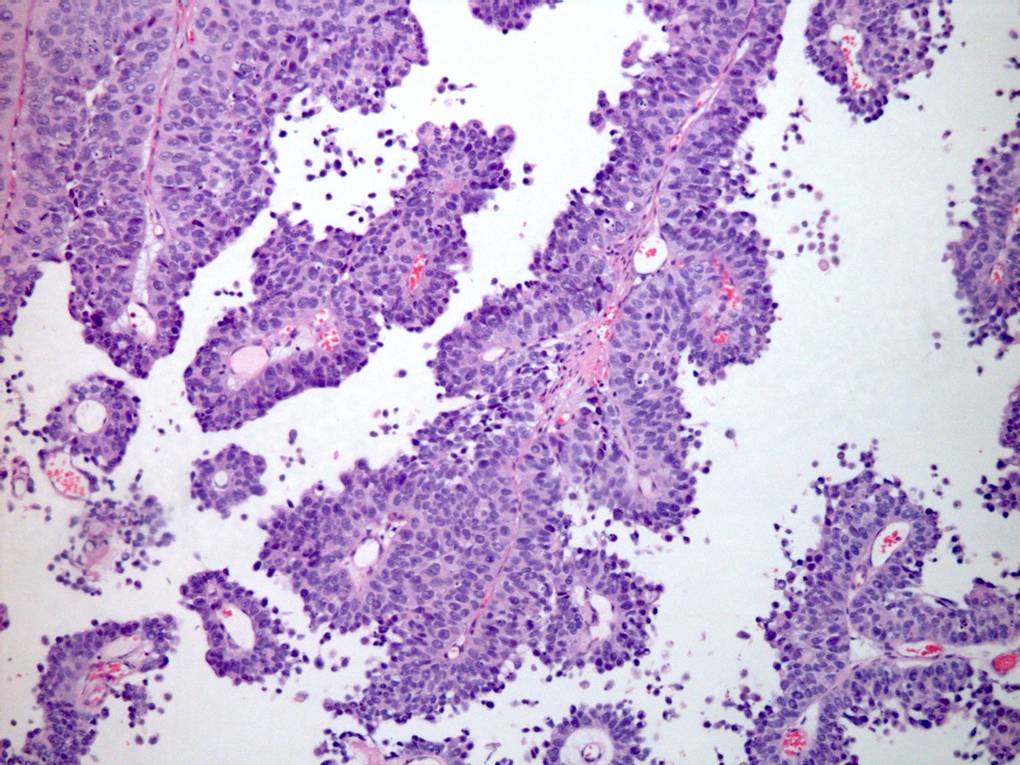

Consensus grade: High-grade papillary urothelial carcinoma (HG-PUC)

Case description (by case creator):

65 year old male. From TURBT. Diagnosis illustrated = high grade papillary urothelial carcinoma